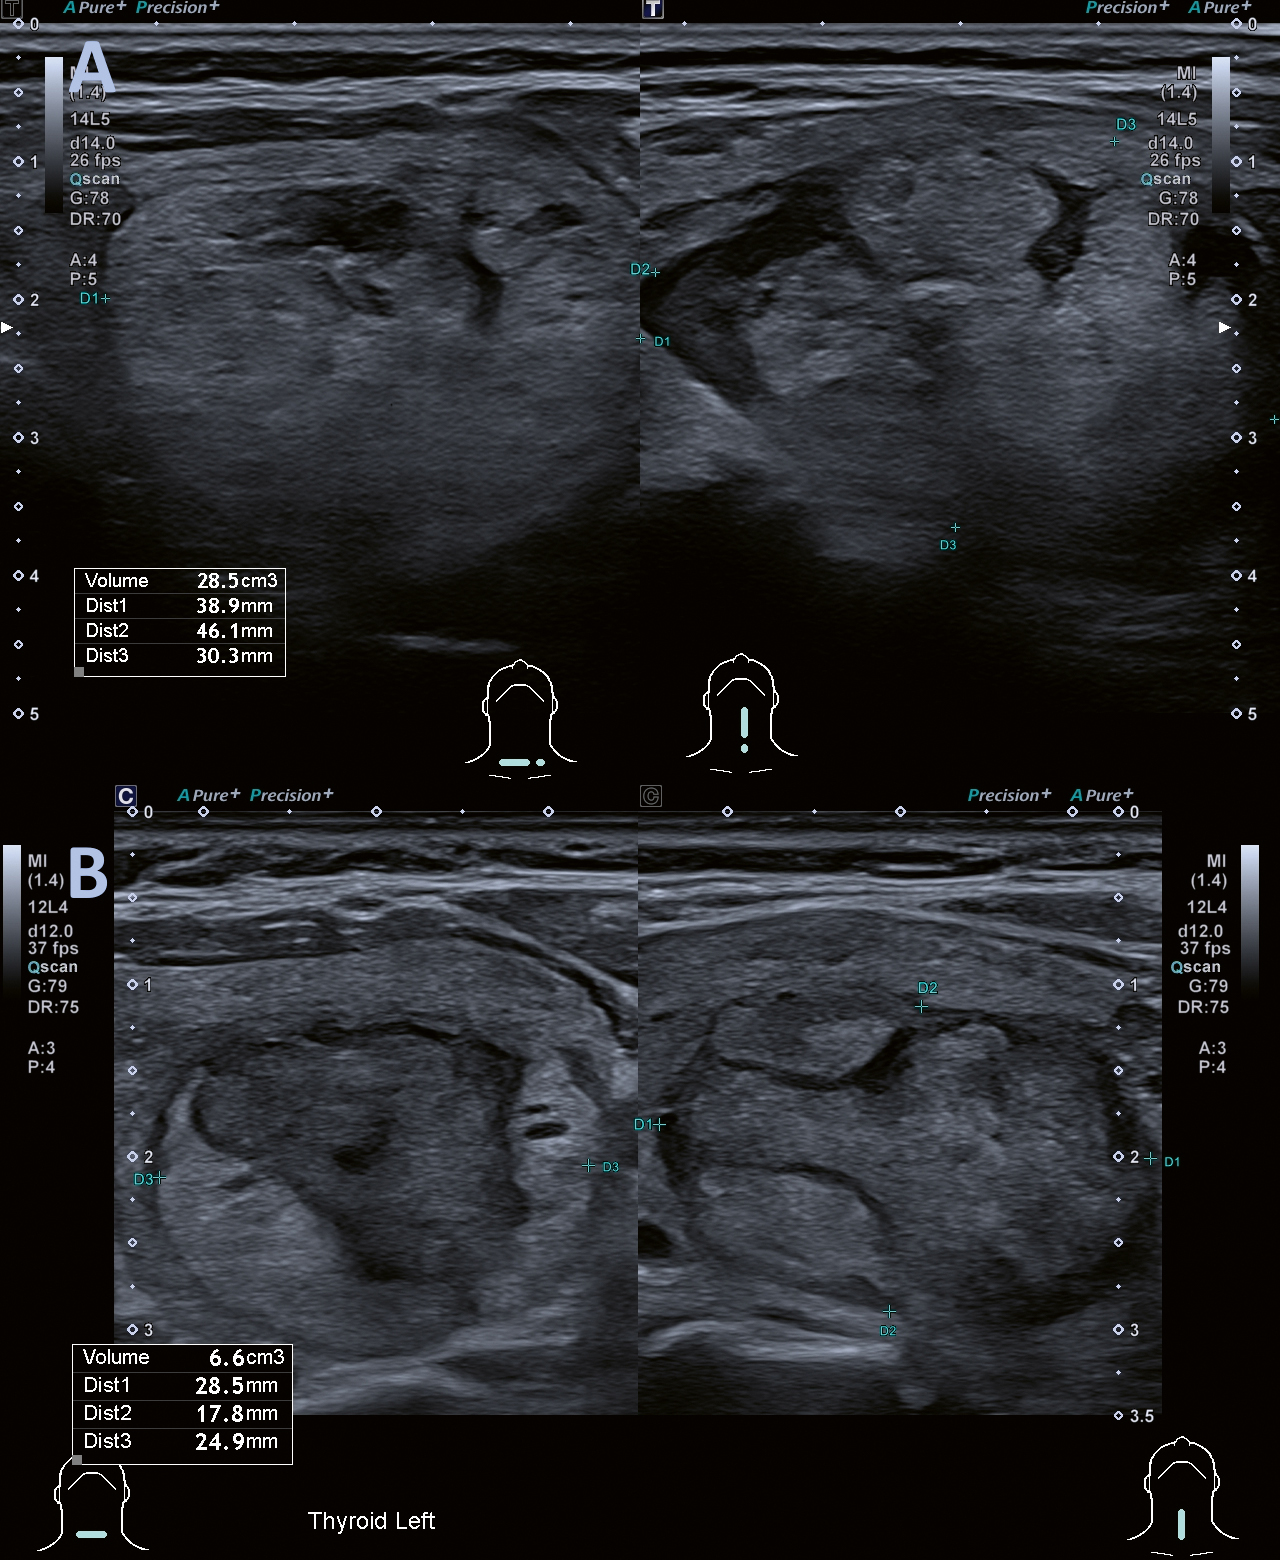

Nodulvolym och symtom utvärderades med ultraljud före behandling (Figur 3A) samt vid uppföljning (Figur 3B) efter 3, 6 och 12 månader. Nodulvolym och -dimensioner fastställdes genom mätning av 3 orto­gonala diametrar (D1, D2 och D3), varpå volymen beräknades enligt formeln: V = (π × D1 × D2 × D3)/6. Volym­reduktionen beräknades enligt formeln: volym­reduktionsgrad (VRR) = [(initial volym – slutlig volym) × 100] / initial volym. Terapeutisk framgång definierades som en volymreduktion på >50 procent vid sista uppföljningen.

Figur 3. A. Volymberäkning inför RFA, patient nr 5. B. Volymberäkning vid 6-månaders­kontroll hos patient nr 5: Volymreduktionsgrad: 76 procent.